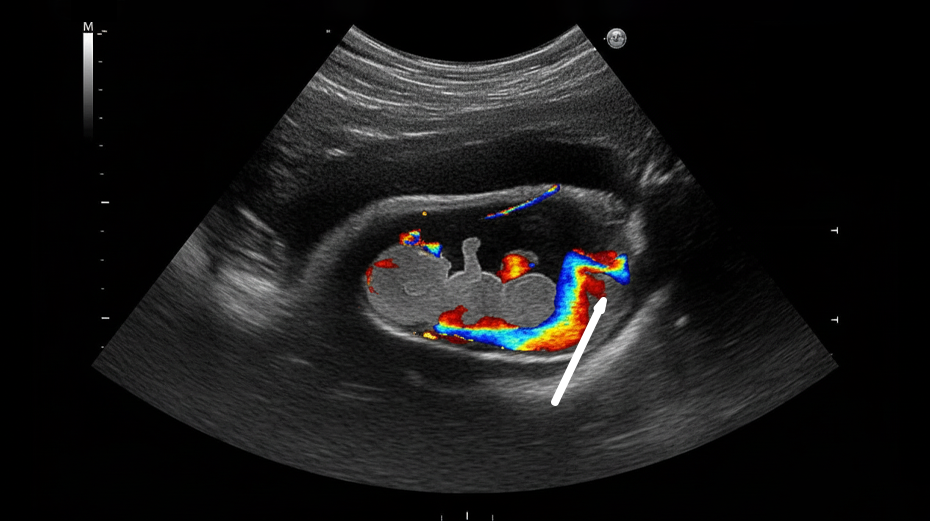

ULTRASONIDO ESTRUCTURAL, GENÉTICO Y DOPPLER

Contamos con estudios avanzados para evaluar la estructura fetal, el flujo sanguíneo uterino y fetal, y la formación de órganos como el corazón, el cerebro y la columna vertebral.

Ultrasonido Doppler en Embarazos de Alto Riesgo

En el tercer trimestre, el Doppler evalúa el flujo sanguíneo entre la placenta, el útero y el bebé, identificando posibles alteraciones en la oxigenación fetal. Es fundamental en embarazos con:

Imagen de arterias

Arteria Umbilical

Arterias Uterinas

Ductus venoso y arteria cerebral media

Este estudio permite tomar decisiones oportunas sobre el seguimiento, la hospitalización o el momento ideal del nacimiento.